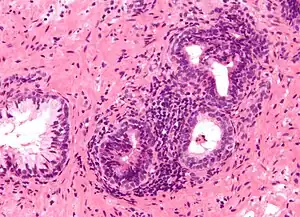

The prostate consists of glandular and connective tissue.[2] Tall column-shaped cells form the lining (the epithelium) of the glands.[2] These form one layer or may be pseudostratified.[4] The epithelium is highly variable and areas of low cuboidal or flat cells can also be present, with transitional epithelium in the outer regions of the longer ducts.[10] Basal cells surround the luminal epithelial cells in benign glands. The glands are formed as many follicles, which drain into canals and subsequently 12–20 main ducts, These in turn drain into the urethra as it passes through the prostate.[4] There are also a small amount of flat cells, which sit next to the basement membranes of glands, and act as stem cells.[2]

Microanatomy of a prostatic gland, showing both luminal cells and surrounding basal cells. H&E stain.

Histology of normal prostate, H&E stain, with benign features: Glands are rounded to irregularly branching, with an inner layer of epithelial cells surrounded by an outer layer of basal cells. They are surrounded by ample stroma.